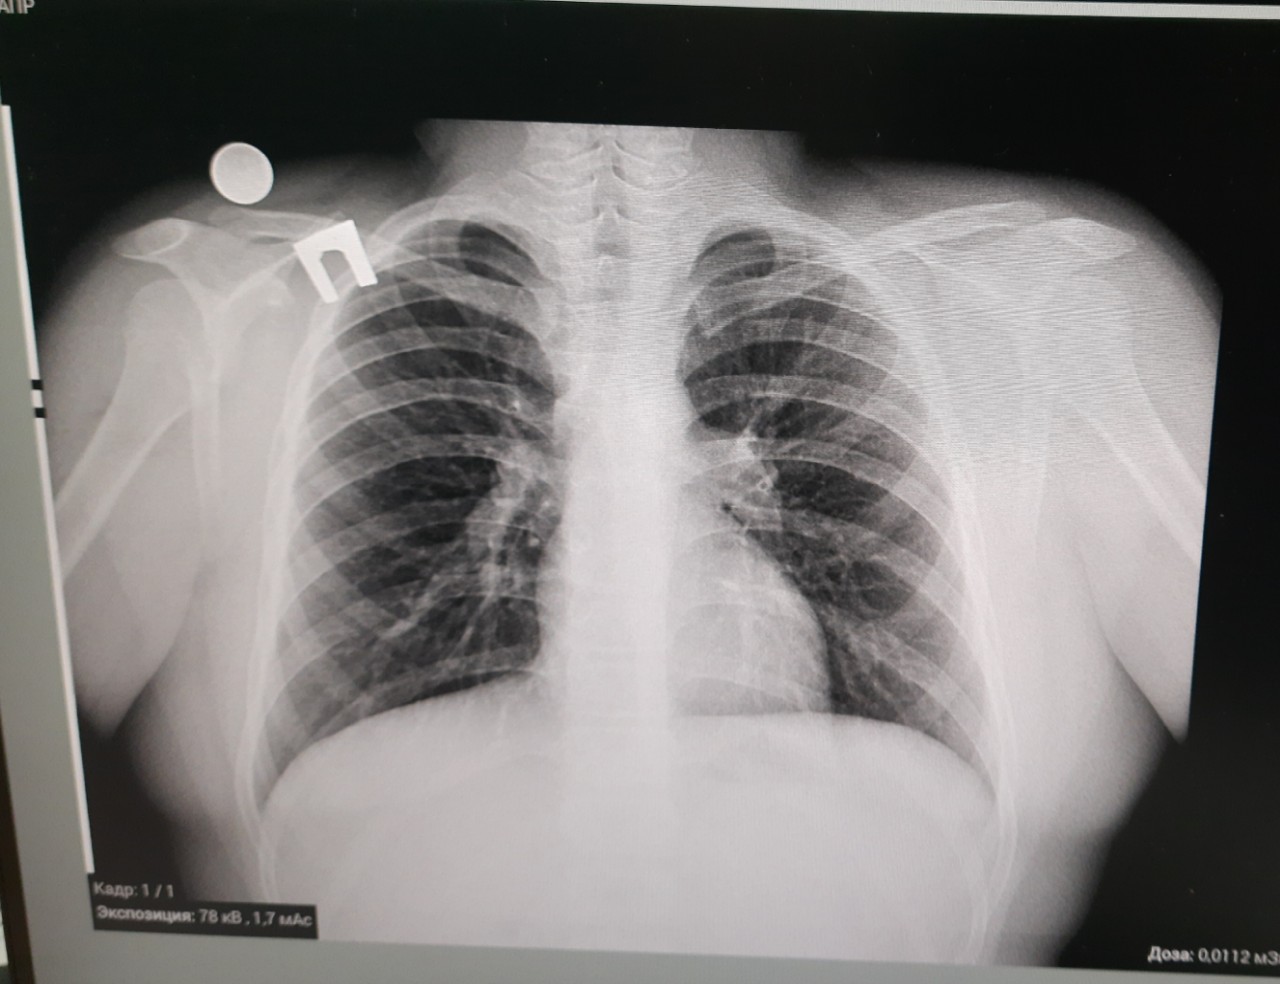

Поражение легких является одним из основных симптомов коронавируса (COVID-19). В данной статье представлены фото рентгеновских снимков, которые позволяют визуально оценить состояние легких при этом заболевании.

Фото рентгеновских снимков поражения легких при COVID-19

На фотографиях рентгеновских снимков видно, как вирус воздействует на легочную ткань. Характерные признаки поражения легких включают пятна, инфильтраты и наличие жидкости внутри легочных альвеол.

Фото рентгеновских снимков помогают врачам и специалистам визуально определить степень поражения легких и принять соответствующие меры лечения и поддержки пациента.